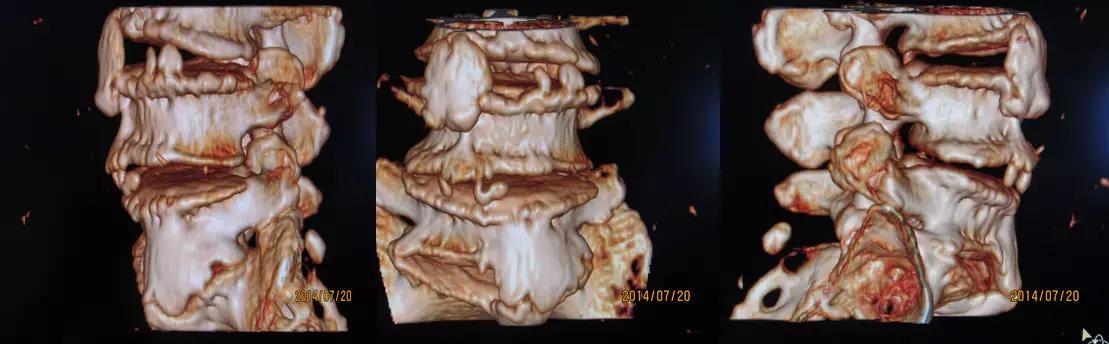

1.颈椎、腰椎骨质增生

骨质增生症多发于中年以上。一般认为由于中年以后体质虚弱及退行性变;长期站立或行走及长时间的持于某种姿势,由于肌肉的牵拉或撕脱、出血,血肿机化,形成刺状或唇样的骨质增生;骨刺对软组织产生机械性的刺激和外伤后软组织损伤、出血、肿胀而致。

颈椎4、5、6椎体最为常见

腰椎3、4、5椎体最为常见

构椎关节骨质增生

腰椎骨质增生VR像

颈椎骨质增生VR像